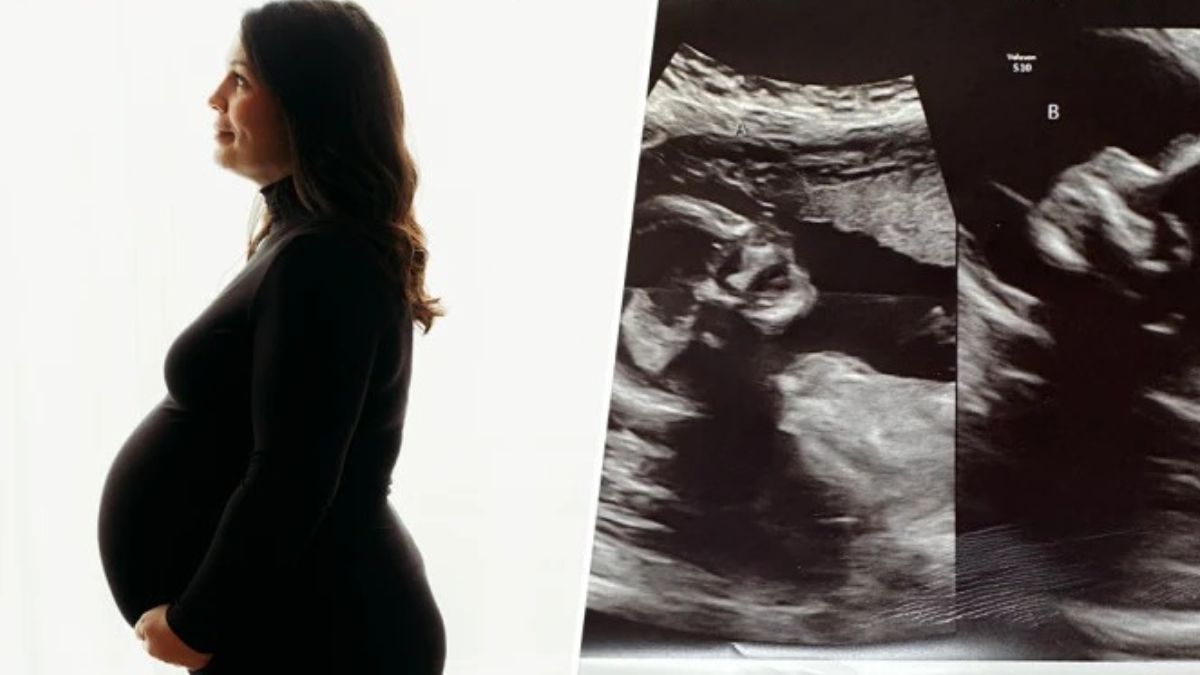

इस महिला के हैं 2 यूट्रस और दोनों में पल रहे हैं बच्चे, 5 करोड़ में से एक महिला को होती हैं ये दुर्लभ स्थिति

Double Uterus Found In Pregnant Woman In US : किसी महिला के जुड़वां या तीन-चार बच्चे एक साथ पैदा होने की खबरें तो आपने सुनी होंगी, लेकिन कभी आपने किसी महिला को दो गर्भाशय होने की बात सुनी। जी हां, अमेरिका की 32 साल की केल्सी हैचर (Kelsey Hatcher) के पास दो यूट्रस है। हैरानी की बात यह है कि उनके दोनों यूट्रस में बच्चे पल रहे हैं।

डबल यूट्रस या दो गर्भाशय की स्थिति को डिडेल्फ़िस कहा जाता है जो अपने आप में दुर्लभ है। लाखों में से एक महिला को यह स्थिति होने की संभावना रहती है। खुद हैचर और उनके पति कालेब भी इसे लेकर शॉक्ड है कि ऐसा कैसे हो सकता है।

इस बारे में हैचर और उनके पति कालेब बताते हैं कि जब वो आठ हफ्ते की अल्ट्रासाउंड कराने गए तो उन्हें पता चला कि वह दो बच्चों की उम्मीद कर रही थी। उनकी मानें तो हैचर जन्म से ही गर्भाशय डिडेल्फ़िस या डबल गर्भाशय के साथ पैदा हुईं। जिसका अर्थ है कि वह दो गर्भाशय और दो गर्भाशय ग्रीवा उनके अंदर है। 3 बच्चों की मां ने "गुड मॉर्निंग अमेरिका" को बताया,'जब मुझे पहली बार पता चला, तो मैंने सोचा कि क्या मैं ऐसे किसी इंसान से संपर्क कर सकती हूं जो इस स्थिति से गुजरा हो।